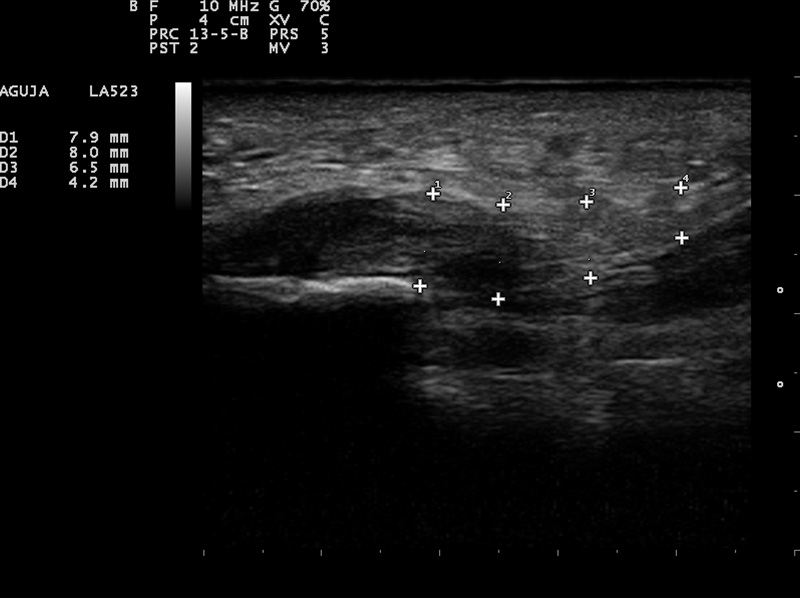

Fascia con normal

Fascia con patología